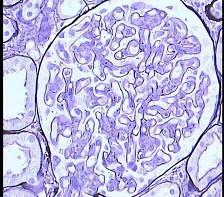

阅读下述三张狼疮性肾炎病理图片后,其病理诊断为 ( )A.Ⅲ型LNB.Ⅰ型LNC.Ⅳ型LND.Ⅴ型LNE.Ⅱ型LN

问题 阅读下述三张狼疮性肾炎病理图片后,其病理诊断为 ( )

选项 A.Ⅲ型LN B.Ⅰ型LN C.Ⅳ型LN D.Ⅴ型LN E.Ⅱ型LN

答案 C